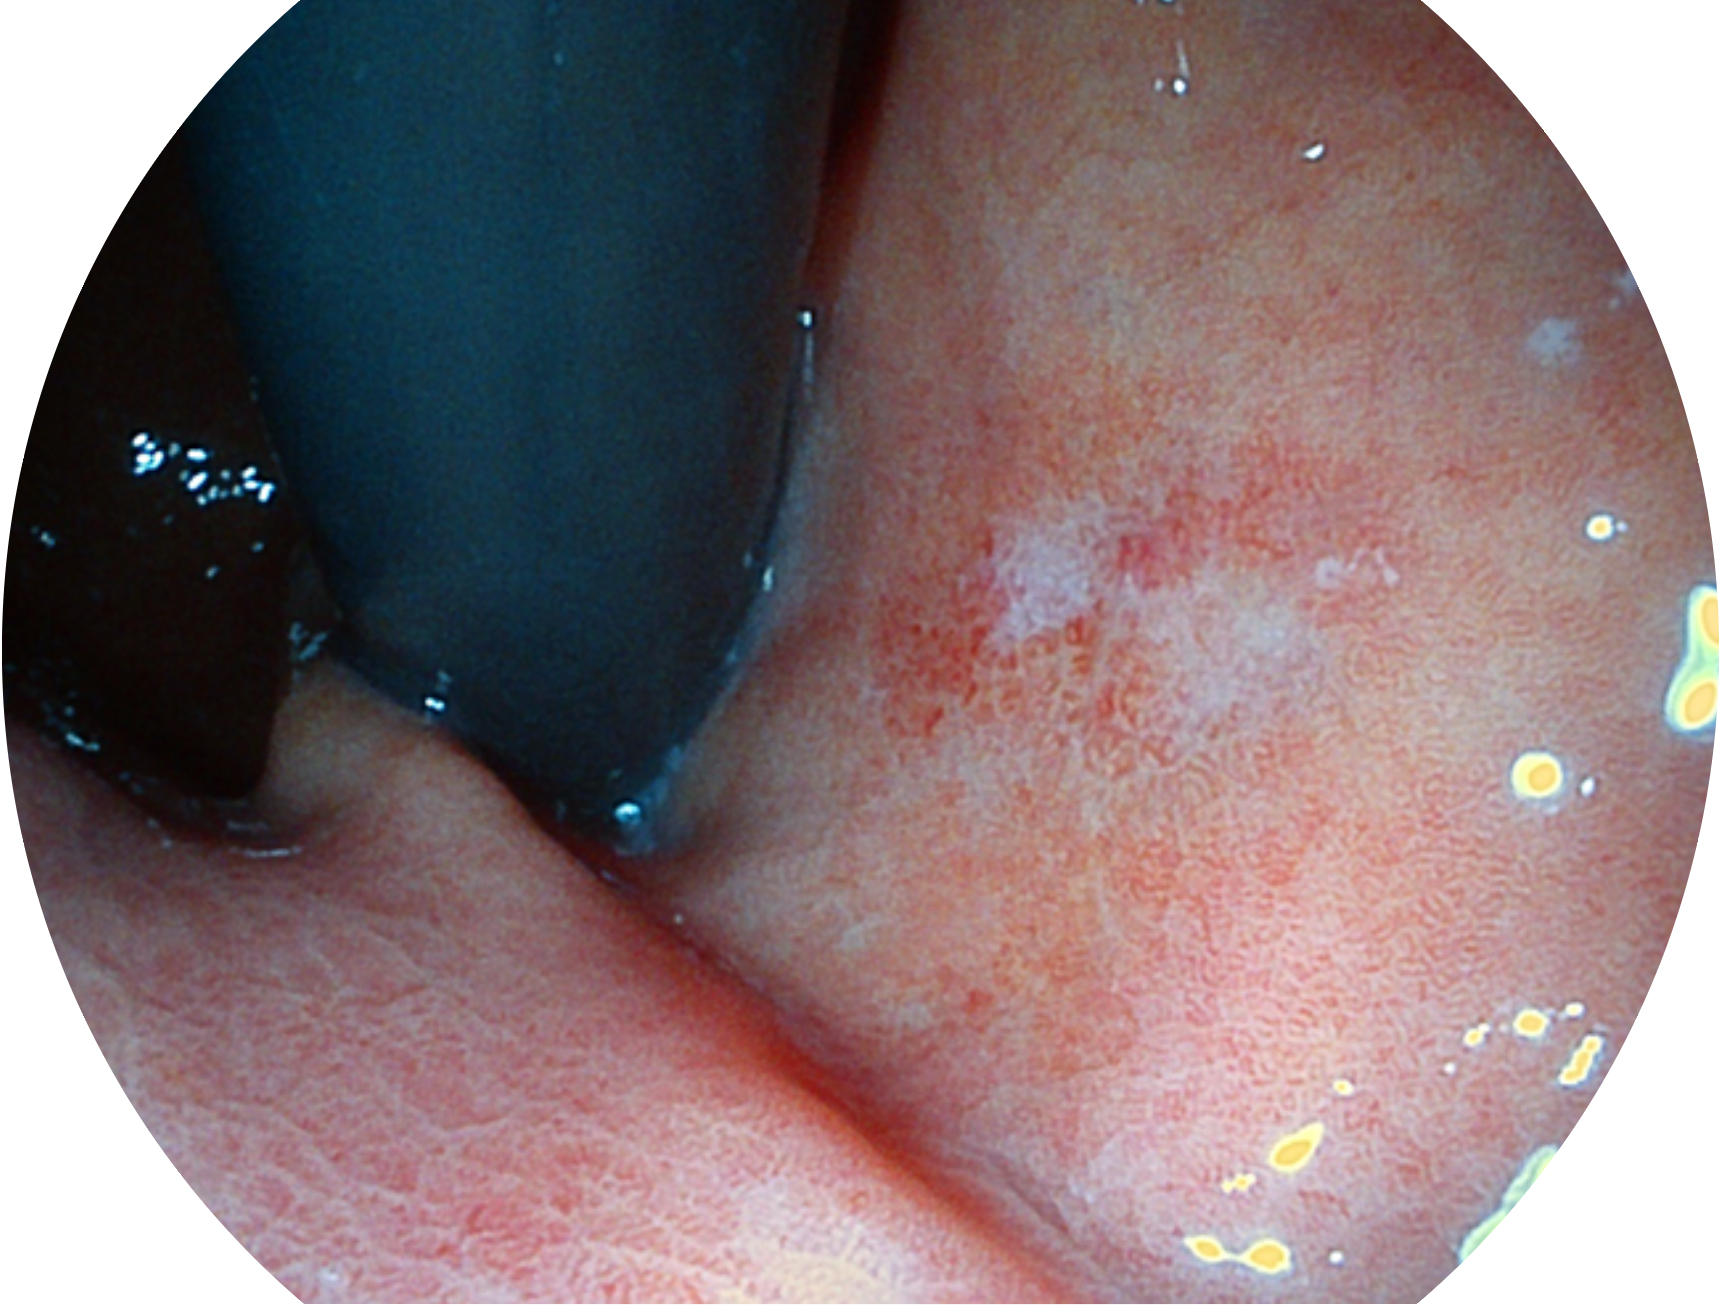

開立新開發(fā)的內(nèi)鏡染色技術(shù),主要是基于多波長(zhǎng)LED 光源的開發(fā),VLS-55Q 四波長(zhǎng)LED 光源是由四個(gè)不同顏色的LED光按照相應(yīng)照明模式所規(guī)定的特定發(fā)光比例進(jìn)行合束后形成,合束后形成的照明光的光譜由紅光、綠光、藍(lán)光及藍(lán)紫光這四個(gè)不同的波段范圍構(gòu)成。具有更高光譜自由度,通過光譜比例的控制,實(shí)現(xiàn)了聚譜成像技術(shù),英文全稱為“Spectral Focused Imaging, SFI”,縮寫為“SFI”和光電復(fù)合染色成像技術(shù),英文全稱為“Versatile Intelligent Staining Technology, VIST”,縮寫為“VIST”。